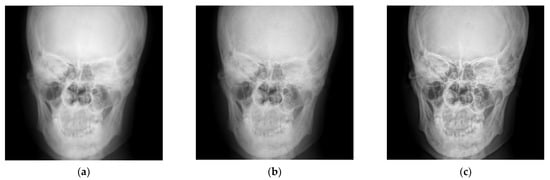

4.1. Simulations for Multicale Diagnostic Detail Enhancement on DR Images